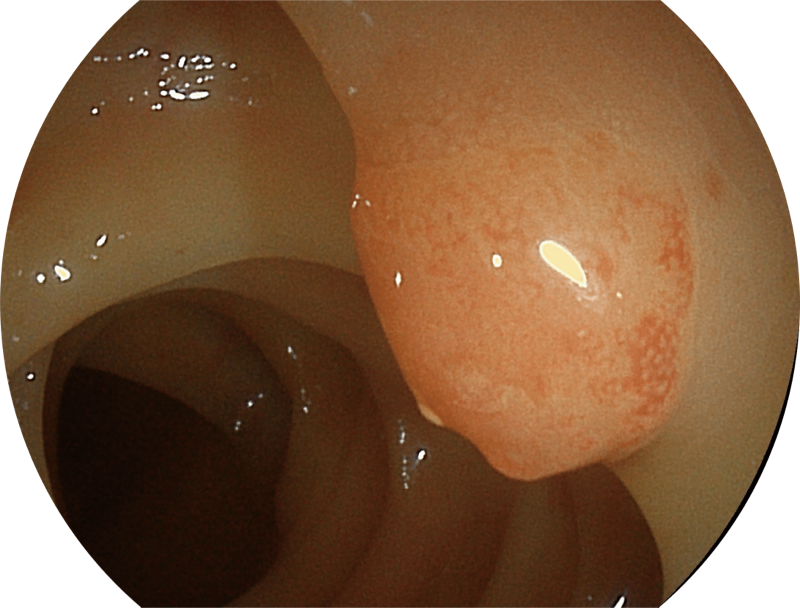

百万级像素高清传感器,1080P全高清视频信号输出,图像清晰。

能够凸显黏膜浅层和中层血管轮廓,适用于中、远景观察下的病灶识别和早癌筛查。

白光图像